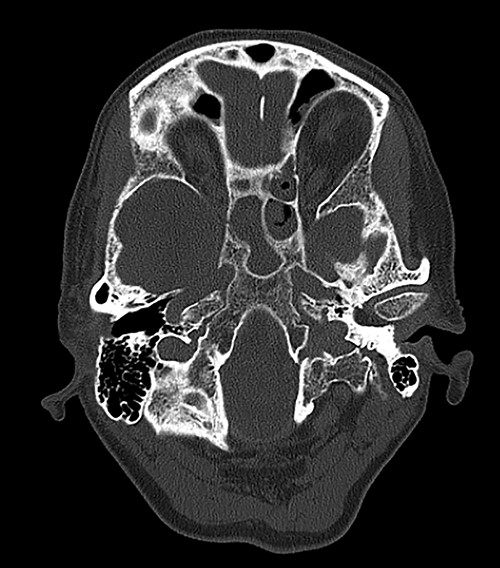

Computed tomography (CT) of the head revealed no signs of meningeal or intracerebral enhancement to suggest an intracranial abscess or cerebritis (Fig. 1).

CT head revealed no signs of meningeal or intracerebral enhancement to suggest an intracranial abscess or cerebritis, but it suggested significant opacification in the paranasal sinuses, particularly in the ethmoid and sphenoid sinuses, most likely indicating a minor post-operative haemorrhage.